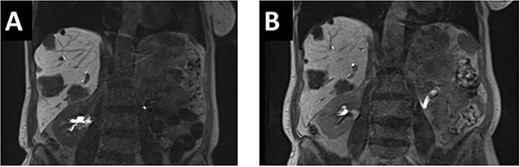

A 65-year-old, otherwise healthy patient was diagnosed with a moderately differentiated adenocarcinoma of the sigmoid colon with a KRAS mutation. Laboratory results showed an elevated CEA of 69 ug/l. Staging of the liver showed multiple liver metastases in all segments with 10 lesions in the right and 8 in the left hemiliver (Fig. 1A).

(A). In the initial pre-chemo MRI of the liver multiple liver metastases in all liver segments could been seen. The largest were in segments II/III (26 mm), V (37 mm) and segment VI (40 mm). (B) After 12 cycles of chemotherapy a size reduction of liver metastasis up to 12% could be achieved. The metastases in liver segments V and VI decreased from 43 to 38 mm and from 37 to 33 mm.

After multidisciplinary tumor board (MDT) discussion, neoadjuvant chemotherapy with six cycles of FOLFOXIRI and Bevacizumab followed by liver-first approach was decided. Restaging after 3 months showed stable disease of the CRLM, therefore, chemotherapy was continued. After 12 cycles, restaging revealed a size reduction of 12% of the CRLM (Fig. 1B). CEA decreased from 69 to 6.1 ug/l. The patient was then admitted to our department for the evaluation of a curative intent CRLM resection. The radiological work-up revealed three remaining metastases on the left- and seven on the right hemiliver. Volumetry illustrated a standardized FLR (sFLR) for a right hemihepatectomy of 30%. In an MDT and the patient was deemed amenable to ALPPS surgery due to the marginal sFLR, bilobar metastases and exceptionally good performance status. Preoperative liver function tests showed normal liver function (LiMAx 450 mcg/kg/h, cut-off >315 mcg/kg/h and ICG R15: 4.0%, cutoff <12%). Although liver biopsy is not routinely performed before ALPPS, MDT recommended a biopsy of the healthy liver to rule out chemotherapy-associated steatohepatitis after 12 cycles of FOLFOXIRI and Bevacizumab in order to ensure a safe liver resection. The biopsy showed signs of subacute hepatocyte demise without fibrosis or cirrhosis. The day after the liver biopsy, the patient collapsed and was admitted to the emergency department of another hospital. CT scan showed a large intrahepatic hematoma (Fig. 2) without active bleeding probably secondary to the biopsy procedure. Due to a hemoglobin drop of 12 g/l a day later and the enlargement of the hematoma in follow-up CT scan, the patient was admitted to angiography, which showed several subcapsular liver bleedings, therefore the right hepatic artery was embolized. Luckily, an accessory right hepatic artery arising from the superior mesenteric artery was present. This enabled us to stay on track with the ALPPS procedure as the right hemiliver would be otherwise without any blood supply (Fig. 3). In synopsis of those findings, the operation was scheduled.